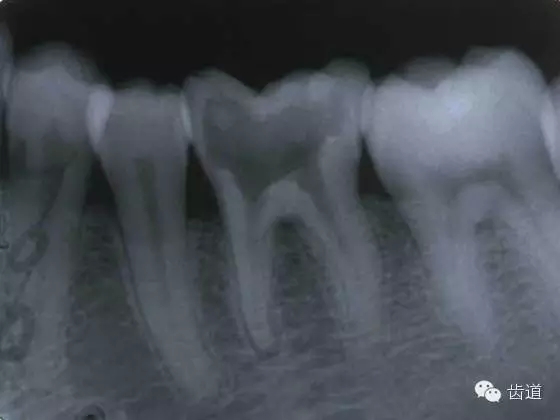

左上7近中頰根器械折斷

右上6腭根器械折斷

折斷于根管內(nèi)的器械要盡量取出,若無法取出經(jīng)常規(guī)充填后,成功率不受明顯影響。

2.器械斷端在根管口內(nèi):用超聲根管銼在該器械旁增隙,通過超聲震蕩和沖洗,可將折斷器械從根管內(nèi)震動沖出。在手術(shù)顯微鏡下直視操作,大大提高了取出的成功率。

3.折斷器械尖端已超出根尖孔:無癥狀不處理;有疼痛則作根尖手術(shù)取出。